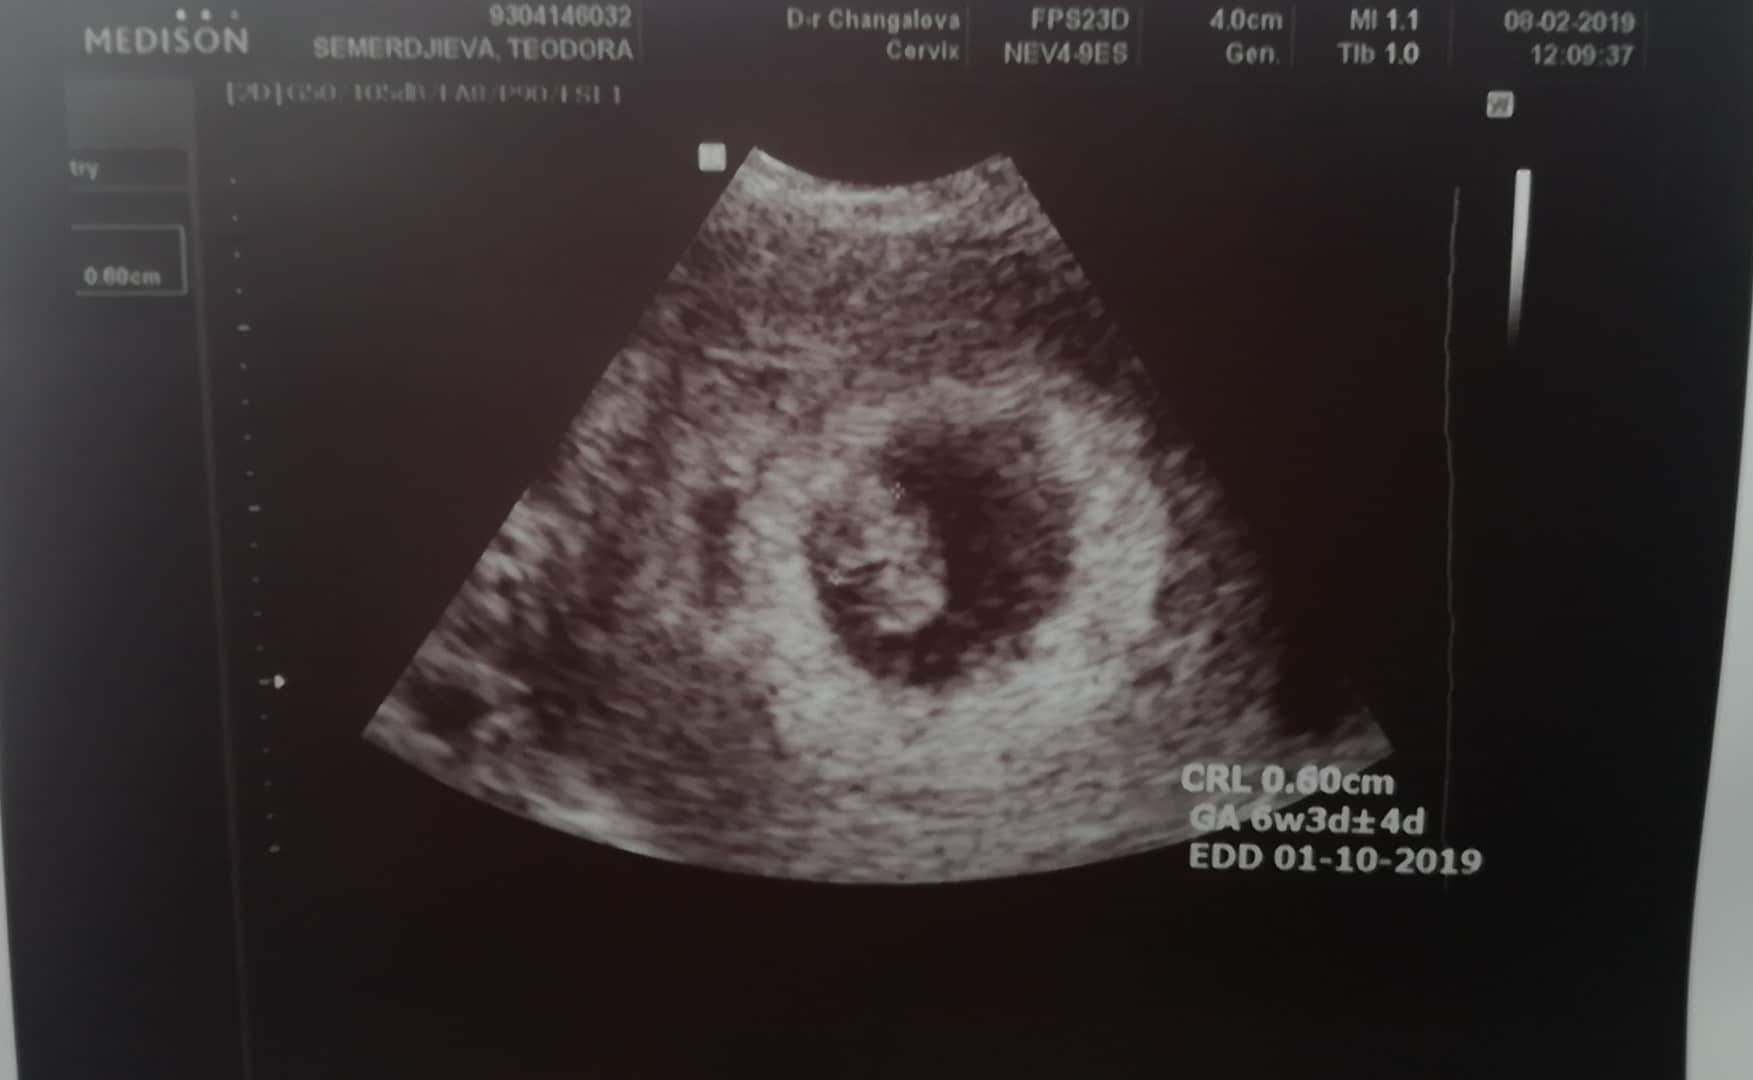

Това е 6 седмица и 3 дни 4Д

А това 7 седмица и 3 дни 2Д

Има голяма разлика нали